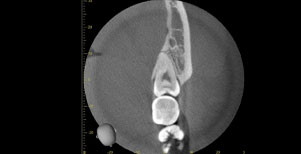

CT

CTで親知らずと神経(下歯槽管)の位置を確認しました。

親知らずと神経は一定の距離があり、麻痺などのリスクがほとんどないと判断できます。